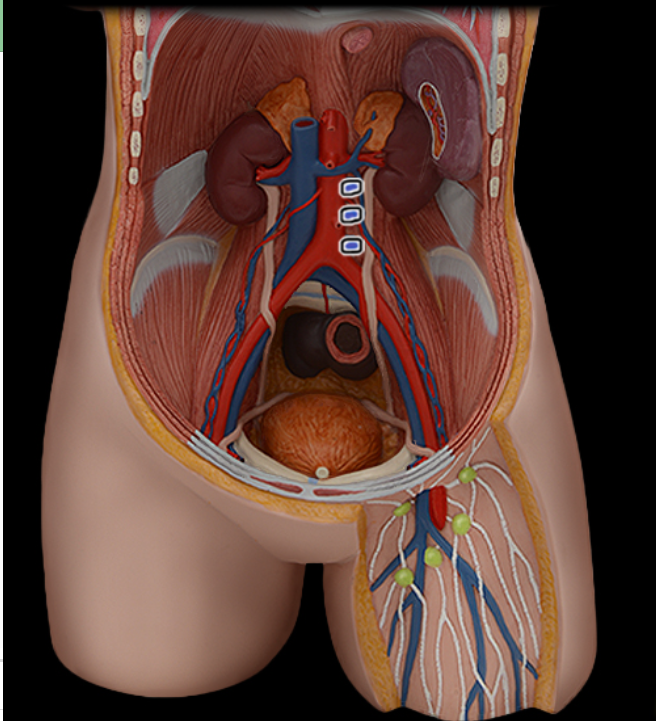

Abdominal aorta

Common iliac a.

Common iliac v.

External iliac a.

External iliac v.

Femoral a.

Femoral v.

Gonadal a.

Gonadal v.

Inferior vena cava

Lumbar a.

Lumbar v.

Renal a.

Renal v.

Superior mesenteric a.